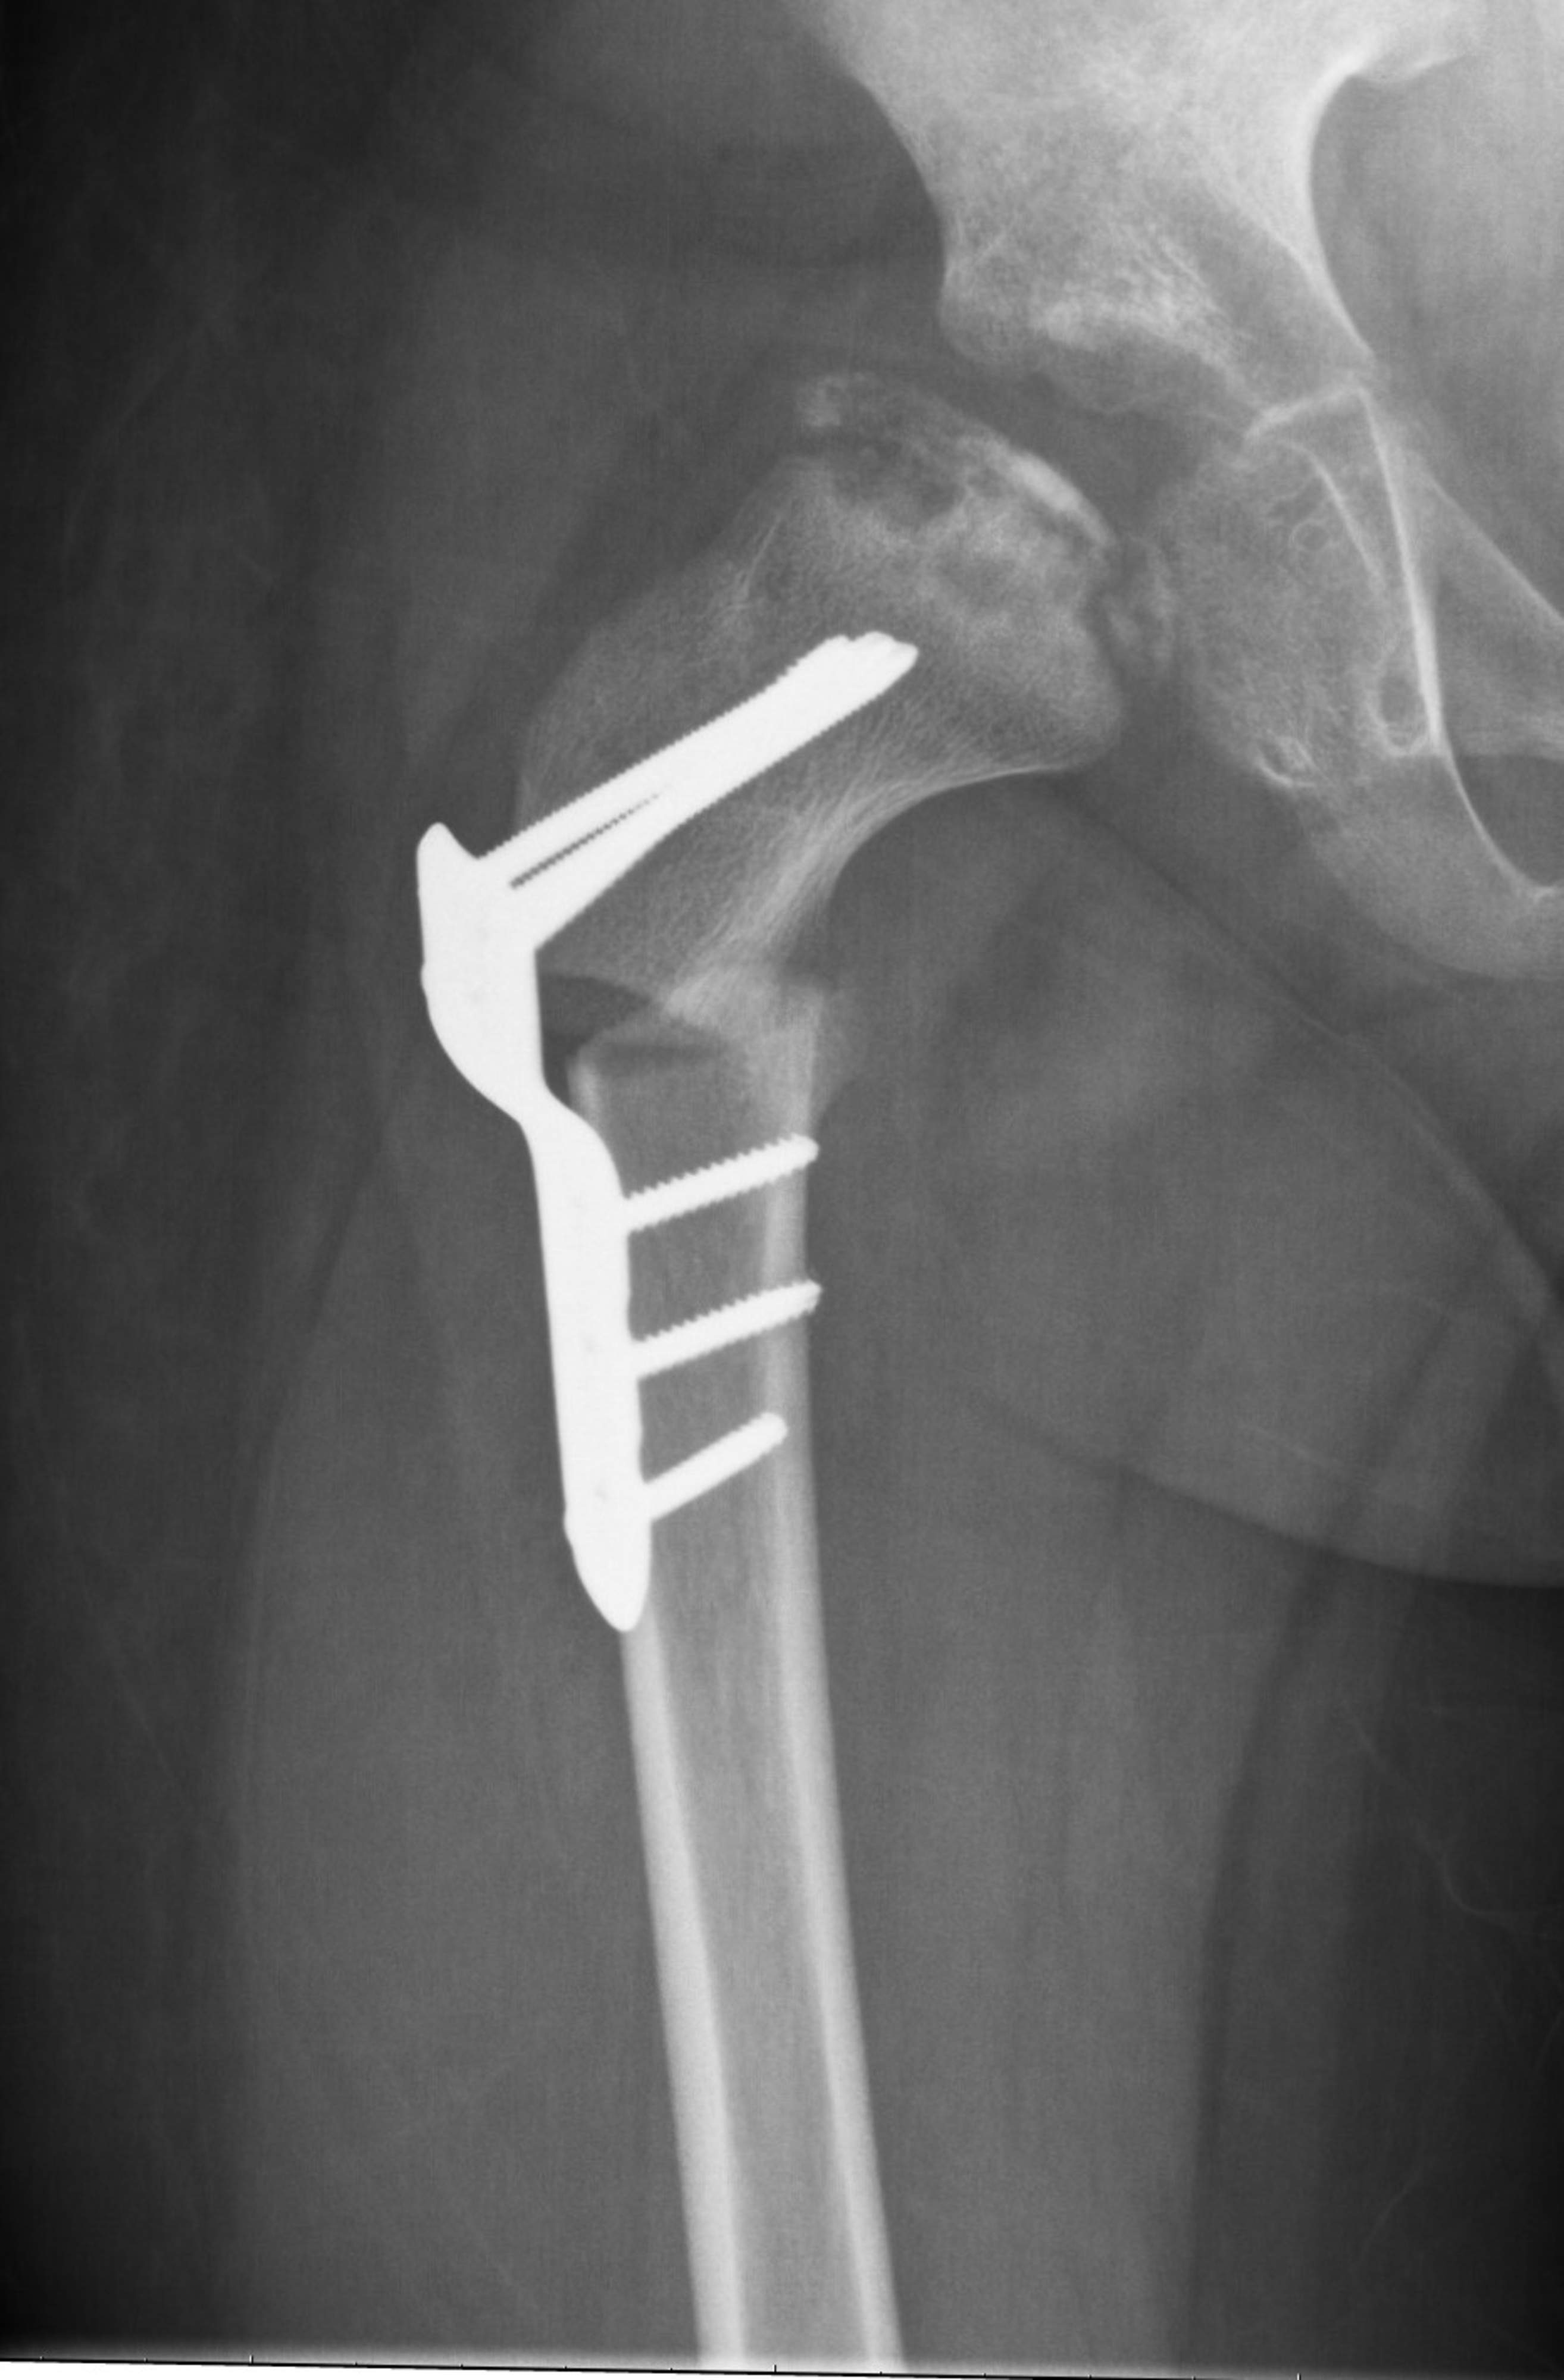

Legg-Calvé-Perthes sjukdom orsakas av en störning i blodcirkulationen i lårbenshuvudet, vars orsak är okänd. Störningen i blodcirkulationen leder till delvis nekros i lårbenshuvudets förbening, på grund av vilket lårbenshuvudets form förändras och det uppstår begränsad rörlighet och smärta i höften. Sjukdomen förekommer hos barn i lek- och skolåldern, oftare hos pojkar än hos flickor. Läkningsprocessen kan ta flera veckor. Prognosen är oftast god om sjukdomen bryter ut före förskoleåldern. I de allvarligaste fallen kan sjukdomen leda till rörelsehinder i höften, benlängdsskillnad och för tidig artros i vuxen ålder.